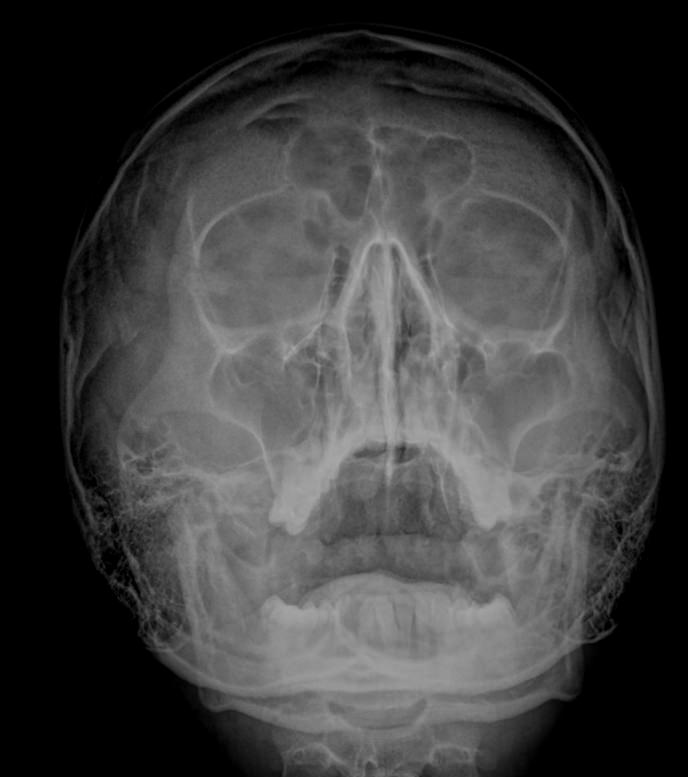

Предпочтительным методом диагностики искривления носовой перегородки является рентгенография. Это безболезненный, доступный и безопасный способ подтвердить искривление и определить его степень. Цифровая аппаратура последнего поколения испускает минимальную дозу излучения, сравнимую с естественным фоном.

Что покажет рентген костей носа при искривлении носовой перегородки

• Утолщение носовой перегородки;

• Искривление хрящевой части;

• Перелом костной части, в том числе со смещением;

• Новообразование, сдвигающее или разрушающее перегородку;

• Костные разрастания на прямой перегородке;

• Отек и воспаление мягких тканей.